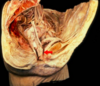

Label A-E of female anatomy [5]

A: bulb of the vestibule

B: levator ani

C: Obturator internus muscle

D: Left ureteric orifice

E: Muscular coat of urinary bladder